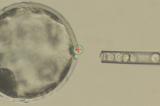

2017 год уже успел отметиться биологической «сенсацией», которая моментально привлекла внимание диванных экспертов: ученые создали химерный эмбрион свиньи с человеческими клетками...